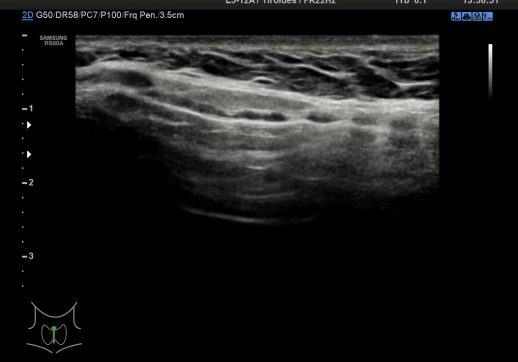

En las siguientes imágenes vamos a ver la segunda parte del estudio del cuello que no es el Tiroides y que es de obligatorio repaso como decíamos en el Post 35 donde hablábamos de las consideraciones básicas a tener en cuenta y detallábamos que otras estructuras se incluían en el estudio del Protocolo de Tiroides.

Para ello vamos a dividir el cuello de la/el paciente que estemos estudiando en 8 regiones así:

Cada región del cuello tiene que tener una foto en el estudio y que puedes ver a continuación, el objeto de esta división es la búsqueda de ganglios locorregionales, así como otros hallazgos extratiroideos que pudieran ser de interés, calcificaciones carotídeas, Tiroides ectópico, incluso las glándulas submaxilares (espacio 1 y 6 pegados al 4) y parótidas (espacio 1 y 6, debajo del pabellón auditivo u oreja).

Con esta división nos garantizamos que repasamos la parte lateral del cuello (1,2,3,6,7,8) y la parte central – superior al Tiroides (4) donde encontramos el Conducto del Tirogloso. También el espacio número 5 o escotadura supraesternal donde pueden ocultarse ganglios o restos del Timo.

Los espacios 1,2,3,6,7,8 siguen la longitud del Esternocleidomastoideo y todas las cadenas ganglionares del cuello.

Debemos permanecer muy atentos a la situación del pictograma y como se corresponde con los espacios del cuello de la foto superior.

En condiciones normales no tenemos que encontrarnos hallazgos patológicos, pero es habitual ver ganglios que no deben sobrepasar el centímetro de diámetro en eje corto para ser considerados normales, todos los hallazgos no normales deben ser registrados para posterior evaluación del Radiólogo/a.